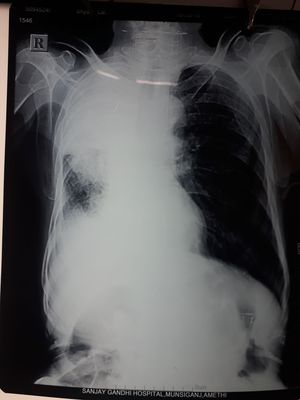

What do u think it is!!!

Tb

Chest

Atelectasis